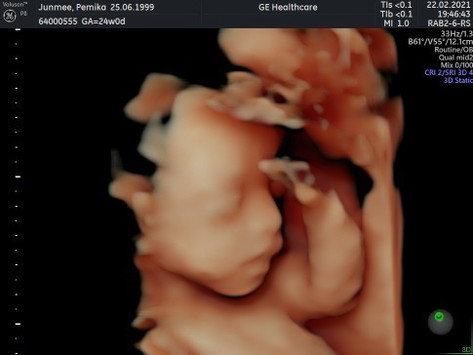

38+5แล้วค้าบ

รบกวนแม่ๆช่วยตั้งชื่อให้ผมทีครับแม่กับป๊าคิดไม่ออกแล้วครับ😂 อีก8วันครบกำหนดคลอดแล้วค้าบ #ลูกชายคนแรก